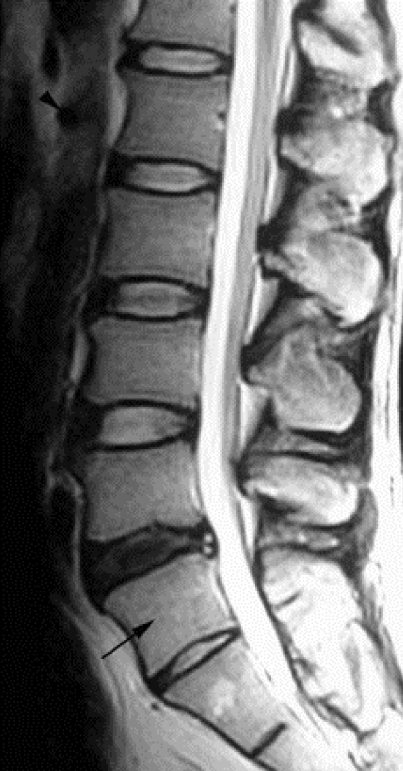

Can You Spot The Serious Back Problem On This MRI?

Herniated diskDo you see it? It’s called a herniated disc, a painful condition that can cause severe sciatic nerve pain. And now you can knock out this painful problem – with a new non-surgical and drugless spinal breakthrough. If you, or your loved one, suffers from disc herniations, sciatica, or back pain you must read these facts at once…